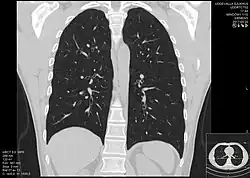

Zobrazovací metody v lékařství jsou techniky umožňující získat informace o morfologii či funkci tkání a orgánů v živém organismu. V humánní ale i veterinární medicíně se používají k diagnostice nemocí a poruch. Existuje celá škála metod založených na principu průchodu ionizujícího záření tkáněmi (RTG, CT, scintigrafie), optických metod (endoskopie), chování látek v magnetickém poli (MRI), akustických vlastností (ultrasonografie) nebo rozpadu radionuklidů ve tkáních (PET, SPECT).[1] Zobrazovací metody se používají i v preklinickém výzkumu či základním výzkumu na laboratorních zvířatech při vývoji nových léčiv, léčebných postupů a pochopení patogeneze nemocí.[2]